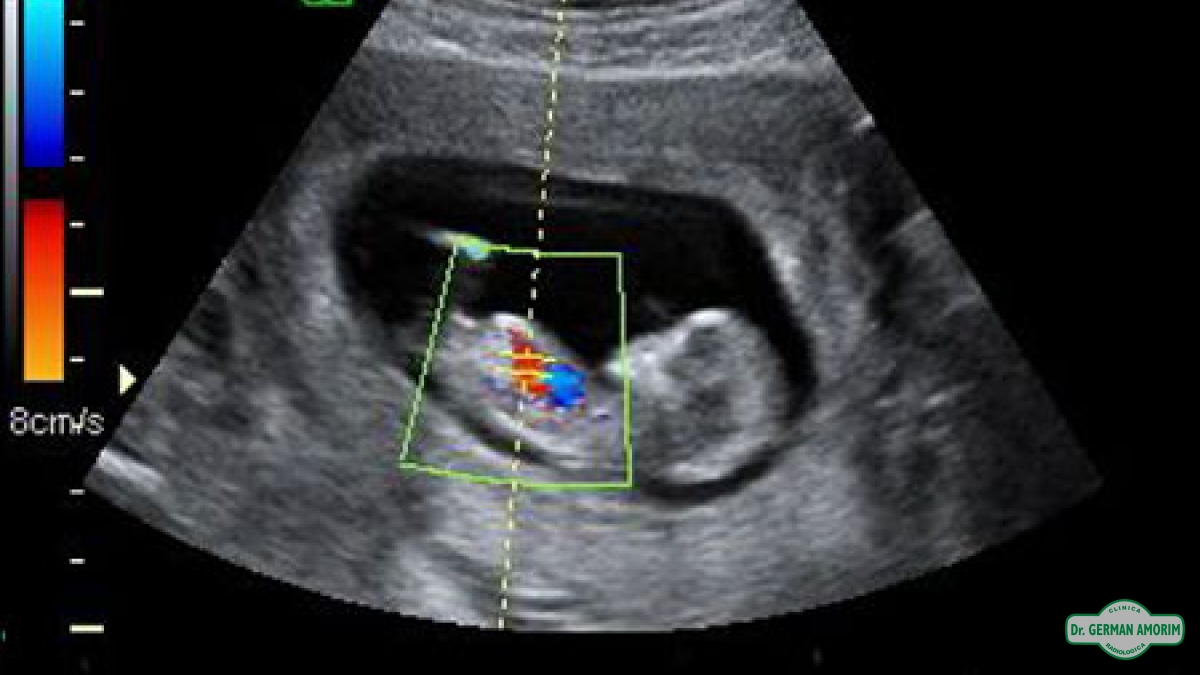

La ecografía-doppler es un tipo de ecografía con la que se estudia el flujo de sangre que pasa a través de las arterias y venas, y que permite conocer su cantidad y velocidad en un momento concreto.

Se convierte en una técnica obligada y especialmente útil cuando se sospechan enfermedades trombóticas de arterias o venas. También se utiliza de forma rutinaria en las ecografías durante el embarazo estudio tiroideo.